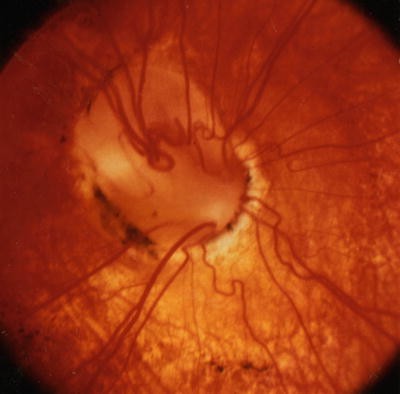

In optic disc coloboma, a sharply delimited, glistening white, bowl-shaped excavation occupies an enlarged optic disc (Fig. 2.18). The excavation is decentered inferiorly, reflecting the position of the embryonic fissure relative to the primitive epithelial papilla [296]. The inferior neuroretinal rim is thin or absent, while the superior neuroretinal rim is relatively spared. Rarely, the entire disc may appear excavated; however, the colobomatous nature of the defect can still be appreciated ophthalmoscopically because the excavation is deeper inferiorly [296]. The defect may extend further inferiorly to involve the adjacent choroid and retina, in which case microphthalmia is frequently present [27, 127]. Optic disc colobomas may contain focal pit-like excavations [378].

Optic disc coloboma. (a) Disc is enlarged. Deep white excavation occupies most of disc but spares its superior aspect. Note chronic serous retinal elevation (seen best at the 11 o’clock position) that has caused subretinal fibrosis. Otherwise, there is minimal peripapillary pigment disturbance in contrast to morning glory disc anomaly. Used with permission from Brodsky [46]. (b) Enlarged colobomatous optic disc (Courtesy of Paul H. Phillips, M.D.). (c) Vertically oval colobomatous disc with atypical vascular dysplasia (Courtesy of Stephen C. Pollock, M.D. and William F. Hoyt, M.D.). (d) Colobomatous disc with infrapapillary defect simulating a double optic disc (Courtesy of William F. Hoyt, M.D.).